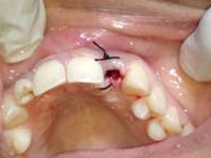

Drilled socket for Implant

Single Tooth Implant